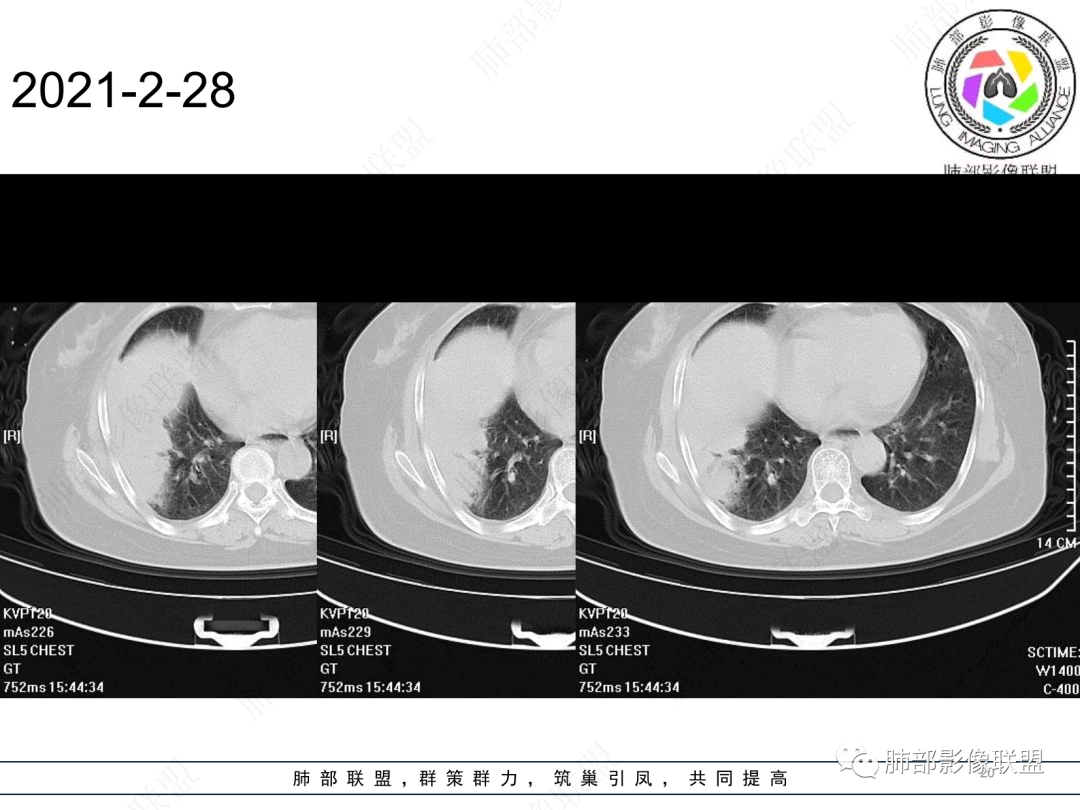

右肺中叶大片实变,内见大片的坏死,中叶外侧段支气管阻塞,相邻胸膜增厚,间隔约四个月后复查,发现低密度坏死内可见气泡影,老年人,反复迁延不愈的病变要考虑恶性,首先考虑腺癌伴感染。鉴别慢性脓肿。

老年女性,慢性病史,炎性指标稍高,肿标正常,右中下肺大片实变,跨叶生长,边界清,收缩力差,膨隆生长为主,支气管杵状截断,均匀强化,其内坏死边界清,可见悬浮气泡,整体观察,病灶膨隆生长为主,邻近肺野无播散灶,形态单一,尽管慢性病史,影像不支持OP和TB,支气管截断呈杵状,肿标正常,均匀强化,虽是高龄患者,诊断恶性肿瘤有点牵强,综和分析,首选炎性病变放线菌感染,其次考虑低度恶性占位炎机母。

这个病例,看长轴、形态,首先跨叶,里面的坏死腔,它是相通的,就是跨中叶及前基底段。

然后中叶与下叶的坏死腔病灶是相通的,病灶是跨叶的,胸膜糊墙为主。

我要看一下下叶。还想重建一下,就是按照我自己理解的长轴去重建出这个病灶的整体形态,我当时一看,好像侧向融合的病灶。侧向融合的病灶考虑慢性炎性病变的,有几种,这样大片的病灶,常规都考虑特殊感染多一些,比如隐球,放线菌,奴卡等,都可以这样的改变。

南边:跨叶、楔形/边缘平直、支气管壁无破坏/连续/局部无膨大、实变区肺动脉走形自然、实性部分均匀、延迟强化、坏死腔内壁光滑/内壁强化环/近端与支气管相通,这些点均支持炎性。所以综合分析:符合炎性。